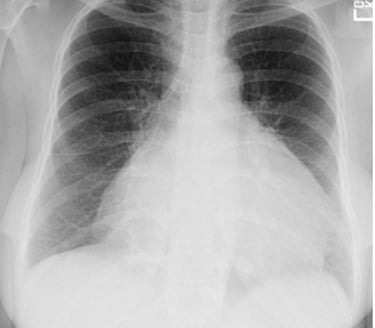

Chest X-ray was requested, and the patient was sent home while awaiting the results.

Question 2. What is the diagnosis ? Differential diagnosis?